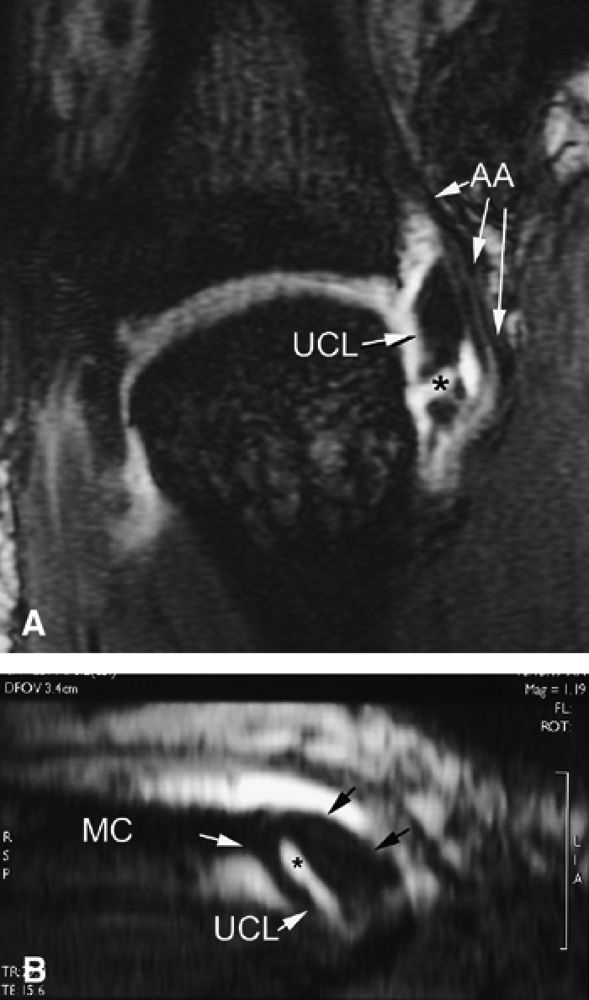

FIGURE 11.8 ● MR arthrography of nondisplaced tear of the UCL of the first MP joint. Coronal (A) and sagittal multiplanar reformatted (MPR) (B) T1-weighted fat-suppressed 3D gradient-echo images showing an oblique tear (asterisk) of the UCL without avulsion. Thearrows mark the distal (black) and proximal (white) aspects of the torn UCL. The sagittal MPR slice is defined along the course of the UCL. MC, metacarpal; AA, adductor aponeurosis.

|

FIGURE 11.9 ● MR of Stener's lesions. MR arthrograms. Coronal (A) and axial (B) T1-weighted fat-suppressed 3D gradient-echo images. The UCL is retracted proximally with a mildly horizontal orientation. The adductor aponeurosis (AA) is partially beneath the UCL. 1 MC, first metacarpal. A more classic Stener's lesion depicted on a coronal proton density-weighted image (C) and a fat-suppressed coronal proton-density weighted image (D), which demonstrate the UCL (arrow) torn from its distal attachment and extending perpendicular to the first ray. The adductor aponeurosis (arrowhead) is seen as a linear structure distal and deep to the torn and retracted UCL.